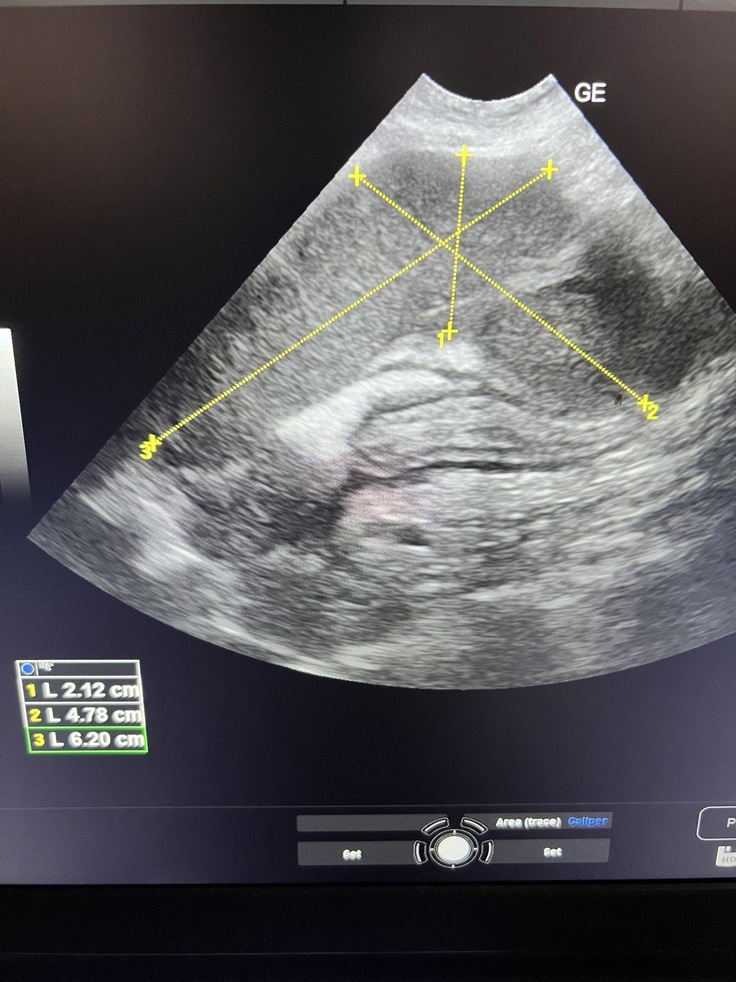

おはぎは、癌で腫瘍が既に6cm以上あります。一つだけではなく、写っていない部分にもあるかもしれないと主治医から言われました。腫瘍は、外科治療で摘出しなければ他の臓器にまで悪い影響を及ぼします。そして、リンパ転移の可能性も有りとの事。その場合、外科手術を受けた後に永久的に治療薬で治療をしていかなければなりません。主治医からは、開腹して癒着が酷い場合には腫瘍摘出が出来ず、そのままお腹を閉じるしかないという最悪なパターンもお話を受けております。その場合には、放射線治療などを検討していかなければなりません。

6月14日

上記↑↑

こちらが、癌腫瘍の診断をされた時の診療明細になります。

エコー検査などを致しまして、

情けないのですが、とりあえず飲み薬で繋いでおります。

腫瘍はこの時で1番大きいので6cm以上。